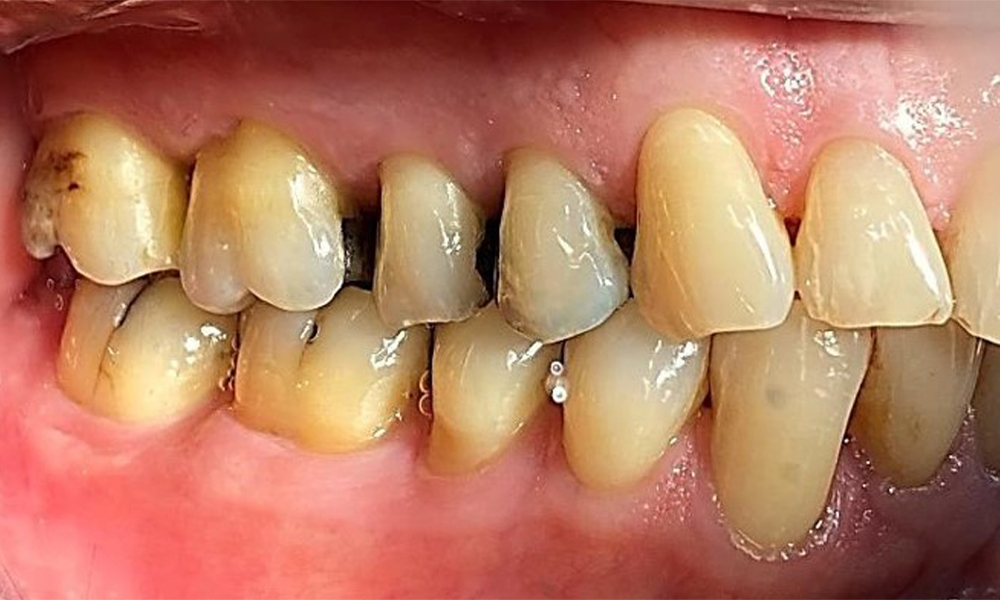

Фронтален изглед със загуба на интерденталната папила между 12 и 11.

Фиг. 2 Фронтален изглед със загуба на интерденталната папила между 12 и 11 © д-р Р. Крапф

Пациентът има пълно съзъбие с 28 зъба, което включва амалгамни и композитни пломби в областта на моларите и премоларите. На зъб 14 има видима клинична маргинална празнина. Зъб 27 има адекватна златна инкрустация. Налице са и генерализирани атриции и абразии. (фиг. 2, фиг. 3, фиг. 4, фиг. 5, фиг. 6)

Пациентът е с пародонтит II стадий, степен В (5). Клиничните дълбочини на сондиране от 1 до 3 mm са във физиологичния диапазон. Локализирани дълбочини на сондиране от 5 mm са наблюдавани медиопалатинално на 17 и 27. Налице са генерализирани рецесии от 1 до 3 mm с частична загуба на интердентални папили (фиг. 2, фиг. 3, фиг. 4)